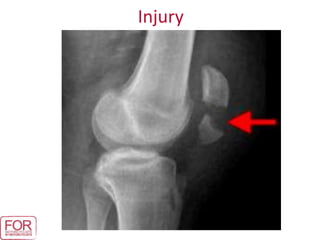

Injuries

• Open fracture to left

humerus.

• Fracture to left shoulder

blade.

• Fractured left

collarbone.

• Left-sided rib fractures.

• Right elbow dislocation.

• Right forearm and wrist

fractures.

• Fractured right

thumb.

• Internal bruising to

the chest.

• Soft tissue injuries to

pelvis.

• Fracture to right

ankle.

• Fractured left heel

bone.